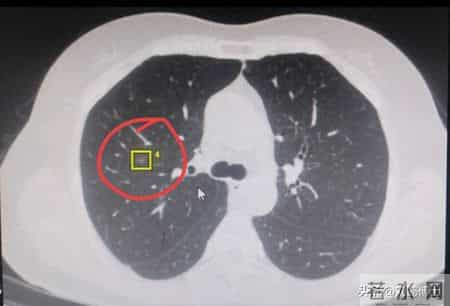

有一位中年女士带着自己的片子过来找我看病,在她右肺上叶有一个直径六毫米的磨玻璃结节,观察过几次也没有什么变化。从形态看,考虑早期肺癌的可能性比较大。她想让我看看自己的肺磨玻璃结节如果做手术,会不会难度很大。

现在这种肺磨玻璃结节都是微创胸腔镜来做,难度并不大,但是大家看她的片子,这个肺结节并不靠近外周,而是比较靠近肺的中心。对于这么小的肺磨玻璃结节,即使考虑恶性的,如果位置太深,预计切除的肺组织很多,我的体会,手术一定要慎重。我建议她手术先别着急做,继续观察一下。

如果这个六毫米的肺磨玻璃结节位置比较靠外,或者靠近叶间胸膜,要做手术切的肺很少,那可以相对积极一些。如果位置太深的话,我还是劝大家要慎重手术,不要着急。